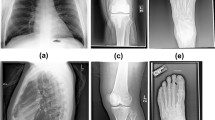

Our algorithm correctly classified 100 % (95 % CI 99.73–100 %) of both the UCSF test images and the publicly available images, based on the Youden Index binary classification scheme. Figure 3 is a histogram of the PFI for the test images, which demonstrates that the network was able to separate the frontal and lateral images. There were several lateral radiographs that were less confidently predicted to be a lateral; despite this, there was still complete separation of classes. Figure 4 demonstrates examples taken from the UCSF and publicly available test sets and the classification probabilities produced by the algorithm.

Transformed images and their classification results are shown in Fig. 6.